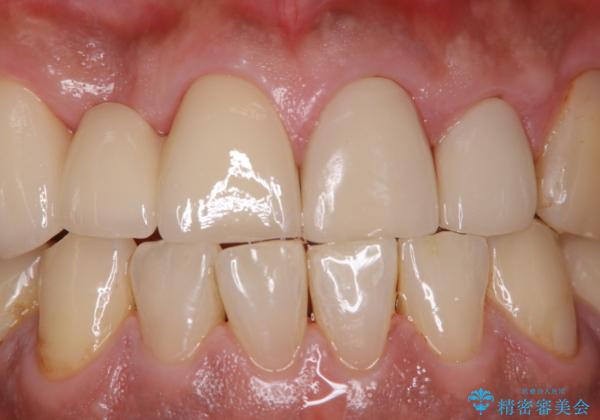

イベント前に綺麗な歯にしたい

- イベントがあるため、なるべく綺麗にしたいとのことで来院されました。PMTC60分コースを行いました。

またPMTCを行うことで、ご自身本来の歯の色になり自然な明るさになります。

口元が自然な明るさになることで、より清潔感のある印象になるため行事やイベント前などにもPMTCを行うはおすすめです。

- 歯を白くする目的の施術ではありません